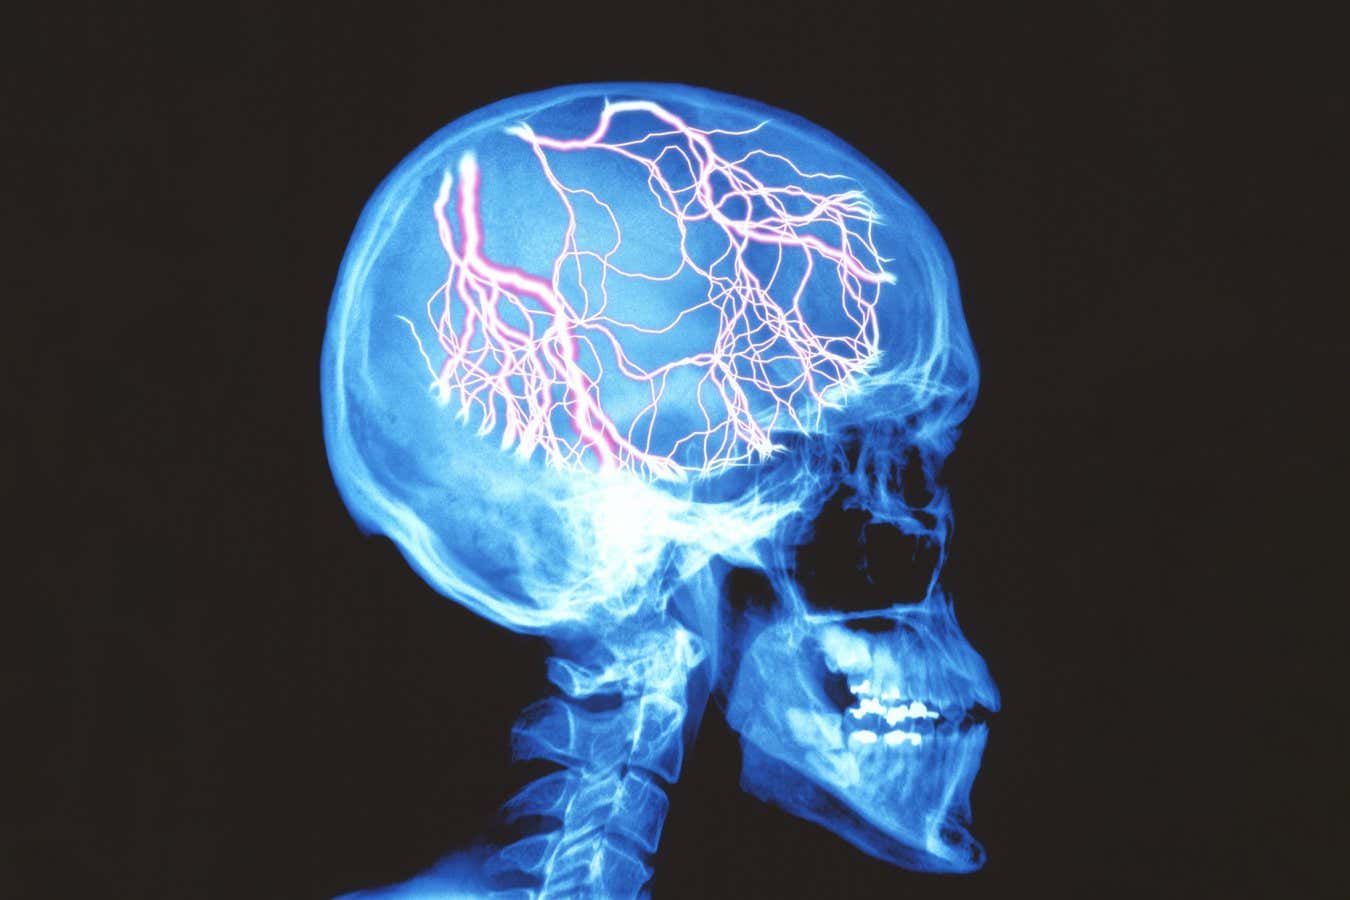

The debilitating nature of migraines can significantly hinder a person’s daily routine

Before migraine headaches decrease in intensity, many individuals experience warning signs such as light sensitivity, sounds, dizziness, and neck stiffness, all of which can significantly disrupt daily activities.